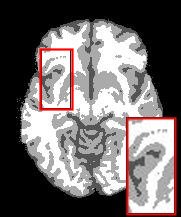

To point out the denoising effect of SegMIC2T based on our model, we produced a visual comparison against MICO and TVMICO on slice064, reported in Figure 5. The figure shows results for two different levels of artifacts: a low level, with noise and no bias, and a moderate level, with noise and level bias. TVMICO seems comparable to SegMIC2T in segmenting noisy slices, but its effectiveness seems to decrease when the noise increases, as we can note in Figure 5 in the highlighted zooms.

| ground truth | MICO | TVMICO | SegMIC2T | |

Figure 3 illustrates the workflow of the algorithm SegMIC2T using the slice060 with low (top row) and moderate (bottom row) levels of the combined artifacts. The noise estimation step splits the original MRI slice into a cartoon image (second column) and a texture image (third column) (1). The correction step, coinciding with the application of the proposed multiaffine ADMM method, produces a denoised and debiased version of the original slice, whose th pixel corresponds to (fourth column). In the last step, the segmentation of the original slice is produced by clustering the pixels in the corrected image (fifth column).